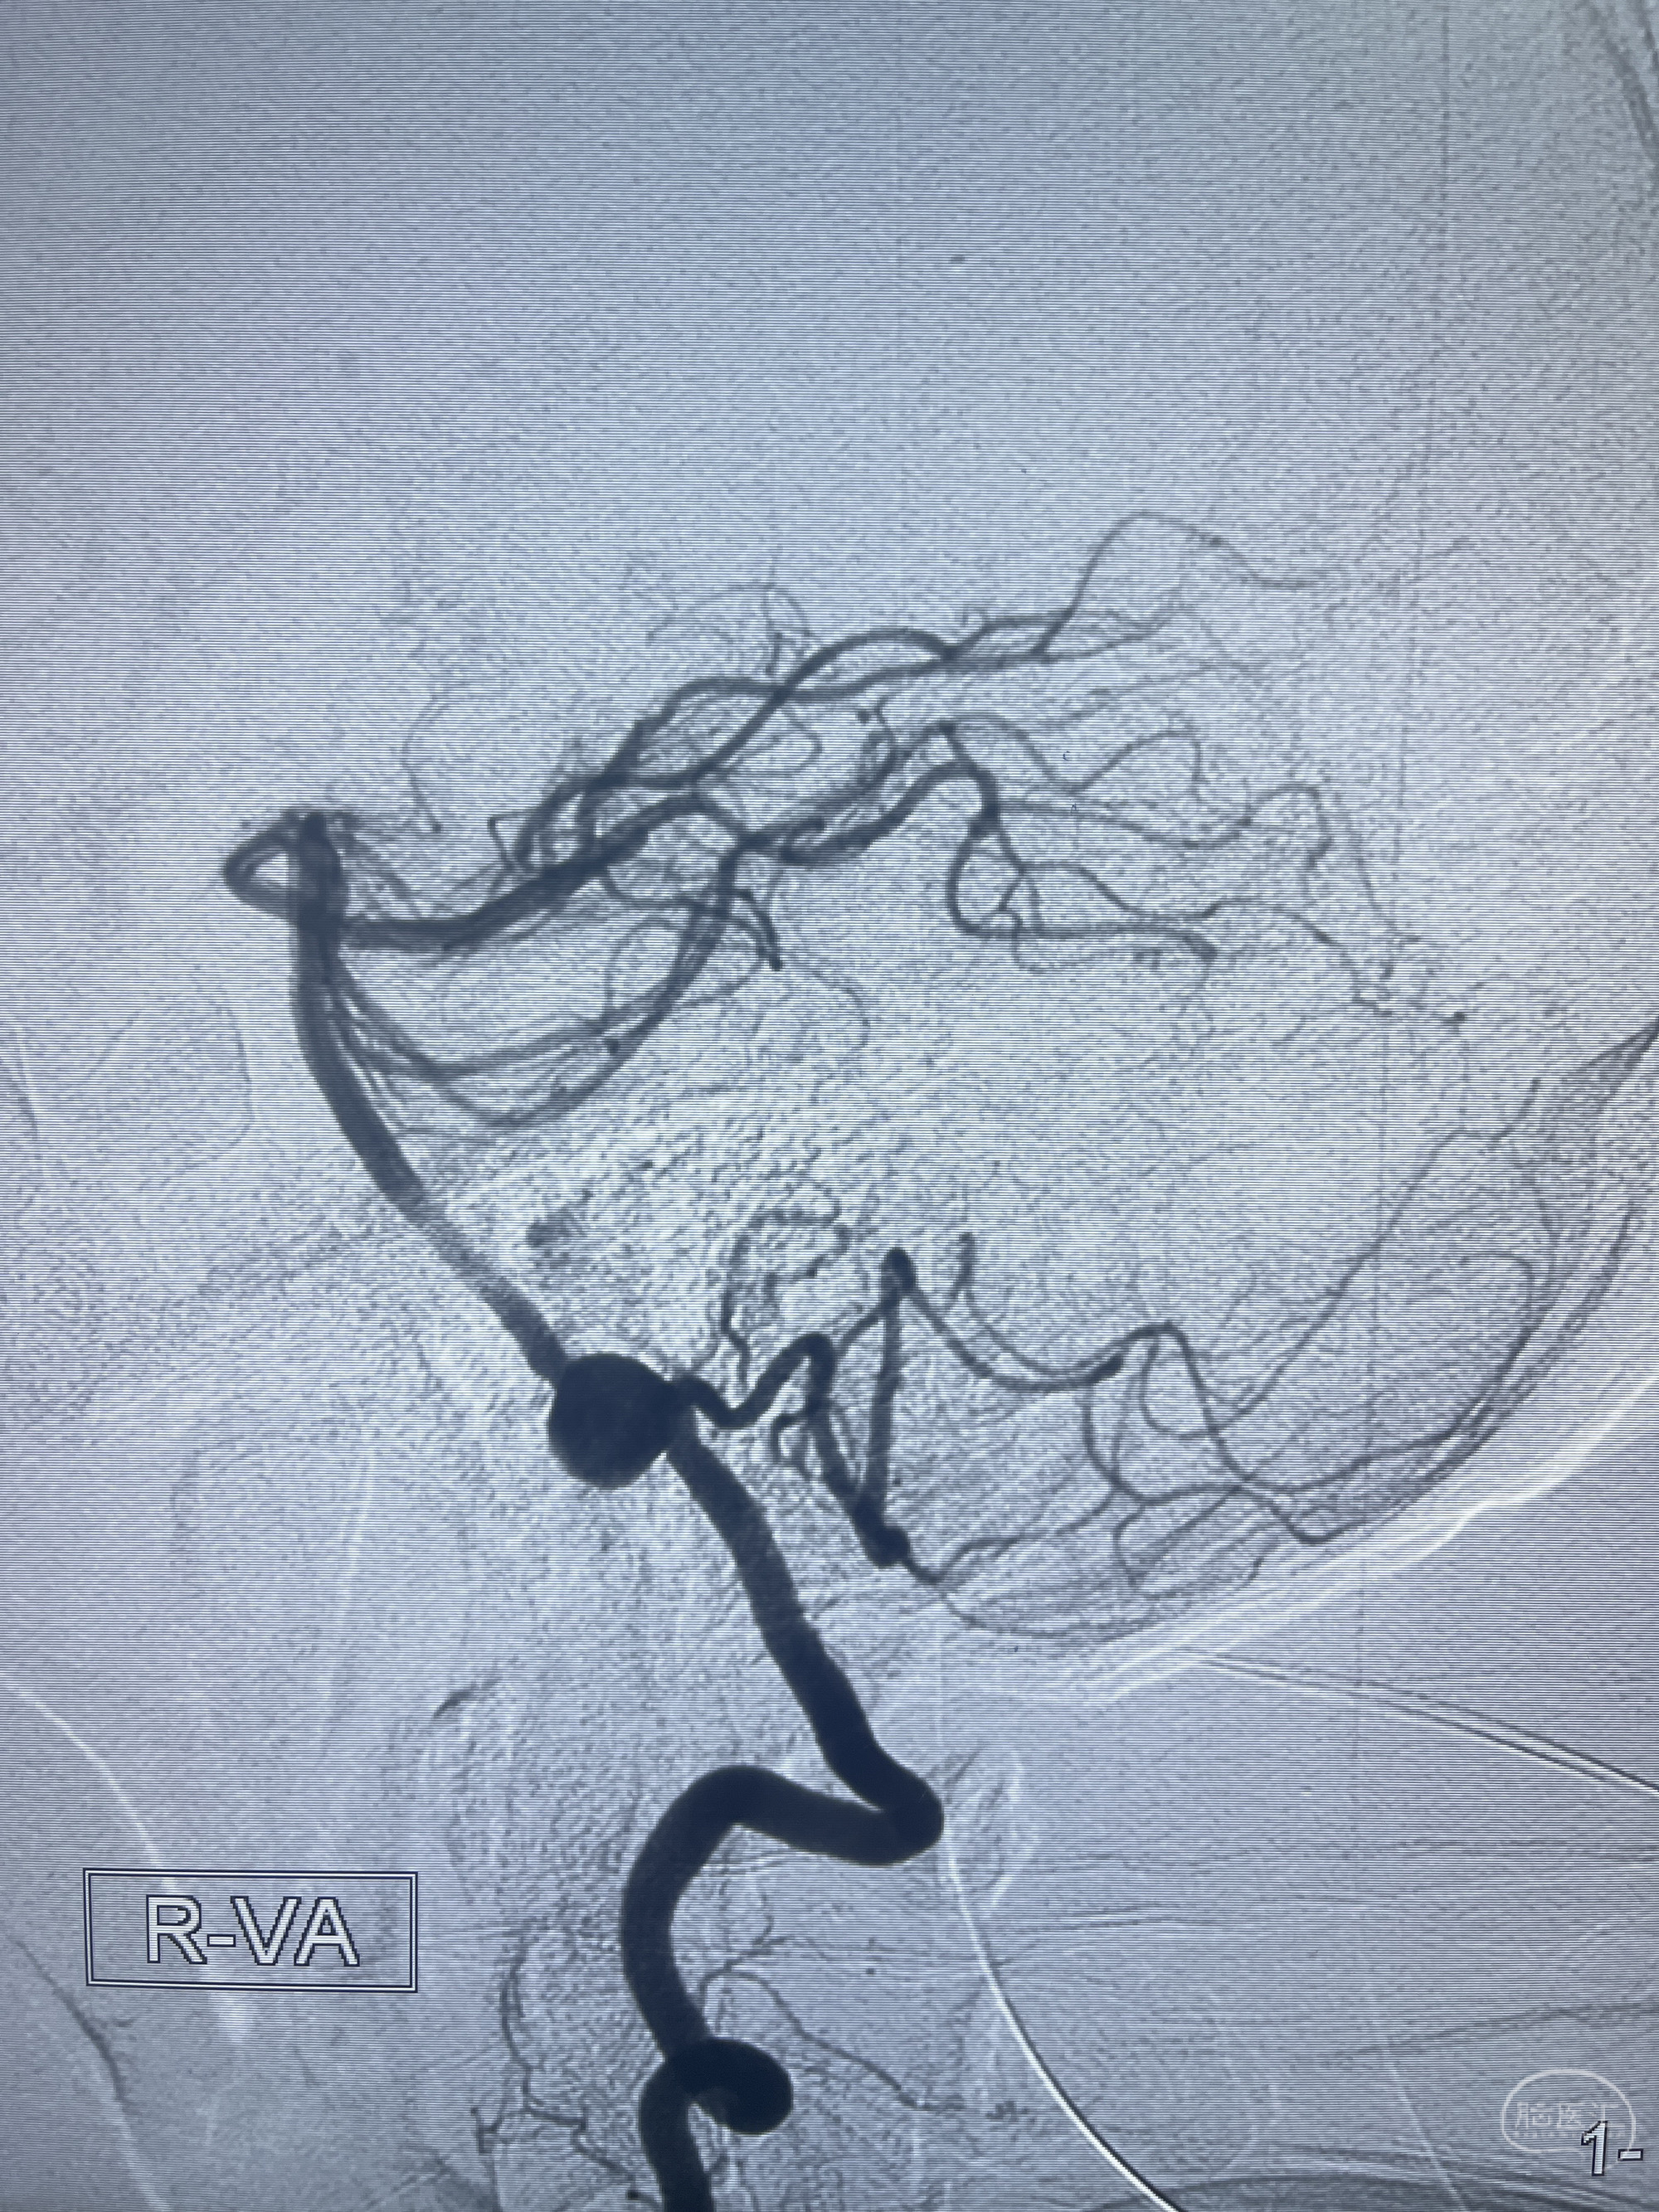

202.04.28脑血管造影:右侧大脑后动脉远段闭塞,右侧椎动脉V4段可见“囊状造影剂填充影”,大小7.64*7.65mm,可见PICA由动脉瘤发出;